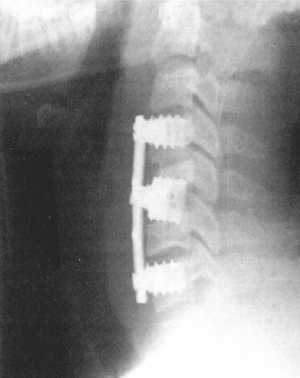

Рис. 3.6. Компрессионный перелом тела

С5 позвонка до и после операции. Стабилизация металлической конструкцией. |